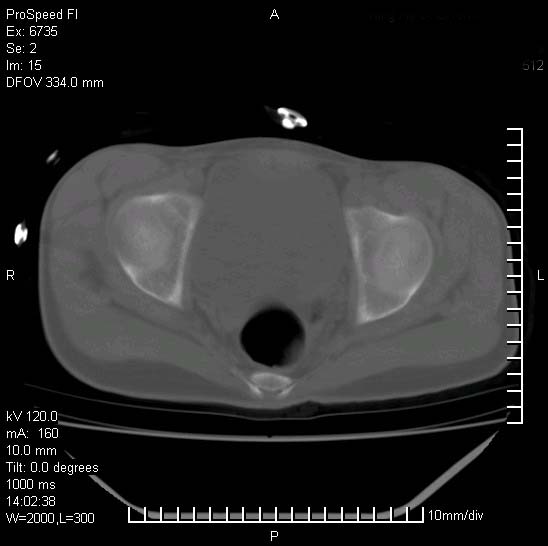

患者自诉胯部疼痛两年余,在当地服用中药,半月前至本院考虑骶髂关节结核,给予抗痨治疗。现发展至右下肢疼痛明显,活动受限,以膝关节处明显,拍膝关节平片无明显异常。

两侧骶骼关节改变,考虑强直性脊炎

左侧骶髂关节面限局性骨破坏,边缘硬化关节腔见钙化物;不出外tb

右侧骶髂关节也有类似改变,只是较左侧轻,首先考虑强直性脊柱炎,不除外结核,建议作hla-b27检查。

典型强脊炎改变,髋关节亦有累及

符合强直性脊柱炎表现。